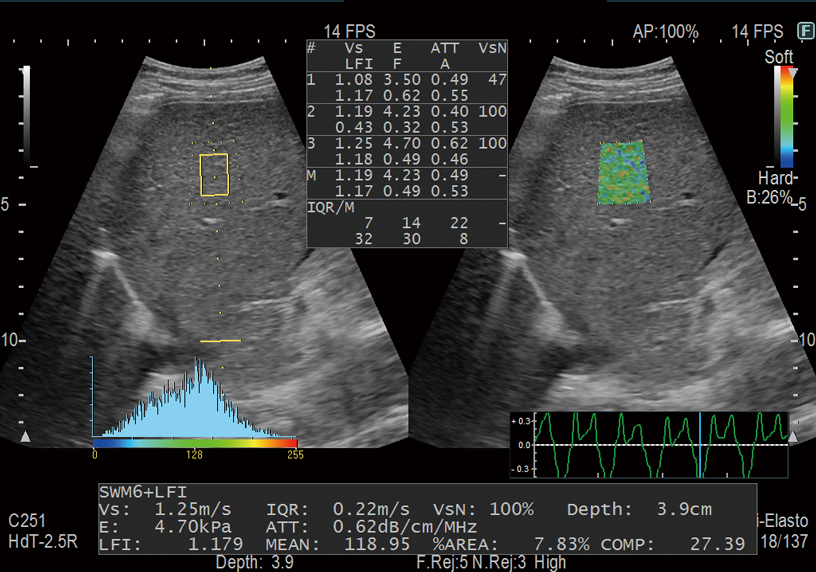

Shear waves are generated using a ‘push pulse’ to excite the tissues. SWM provides an assessment of tissue stiffness by calculating Vs, the propagation velocity of the shear waves. SWM provides an additional reliability indicator, VsN, as an objective evaluation of the Vs measurement. SWE color-codes tissue sttifness based on the propagation velocity of shear waves. SWE can be used to evaluate liver visually and non-invasively.

By integrating the two non-invasive methods for evaluation of liver tissue stiffness, namely RTE and SWM, it is possible to assess the chronological progression of liver inflammation and fibrosis with greater accuracy. A combined simultaneous estimation of the degree of steatosis (ATT index) makes Combi-Elasto a comprehensive tool for the differential diagnosis of liver disease.